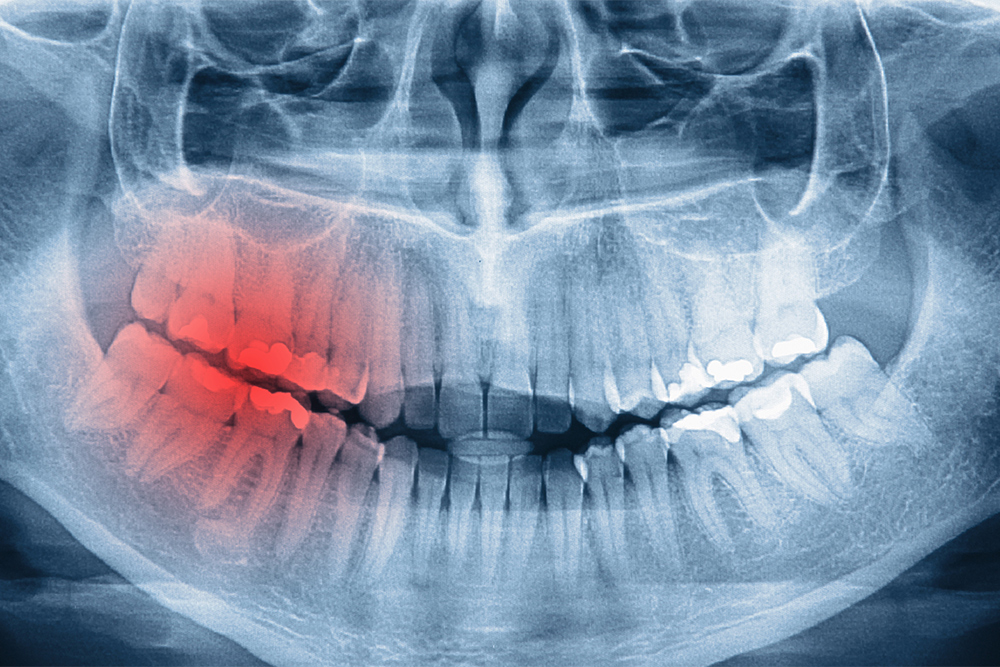

在牙科門診中,牙裂是讓醫師與病人都感到相當棘手的問題,它不像蛀牙可以透過X光片輕易察覺,有時甚至像個隱形殺手,平時沒事,一旦咬到特定角度就鑽心劇痛,隨著飲食習慣改變(喜好硬食)與生活壓力增加(磨牙症),牙裂的發生率正逐年攀升。